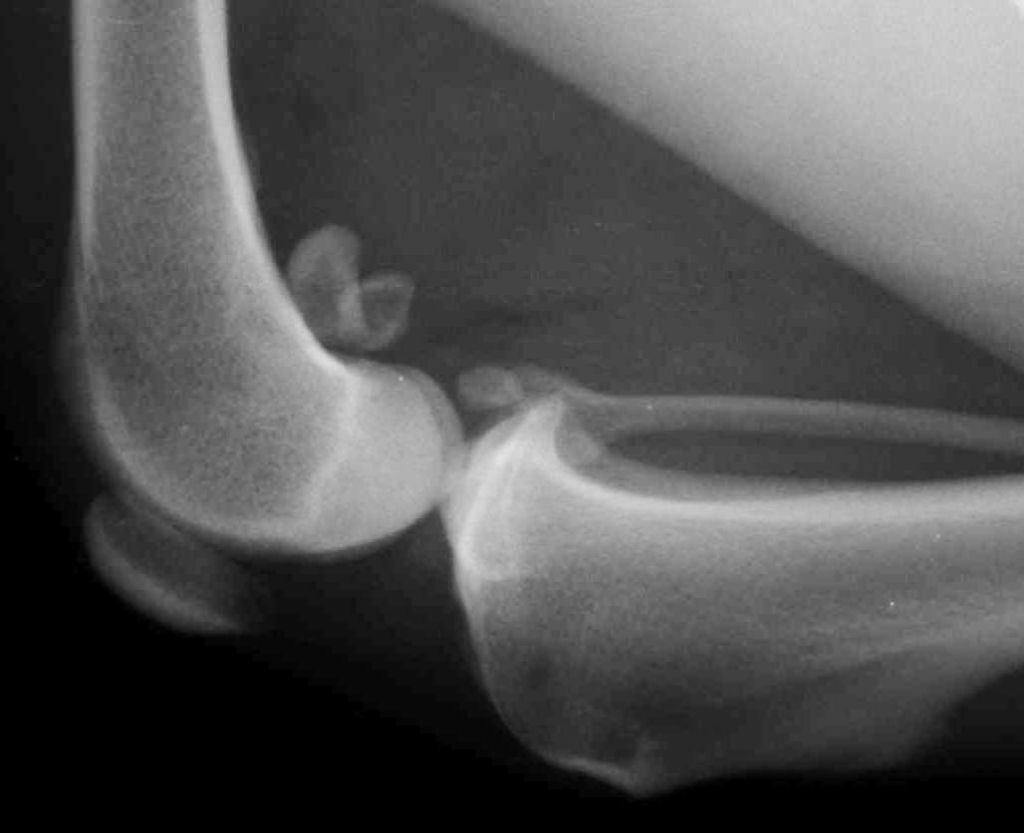

У статті я розповім про таке захворювання, як артрит у собак. Перерахую причини розвитку цієї недуги.